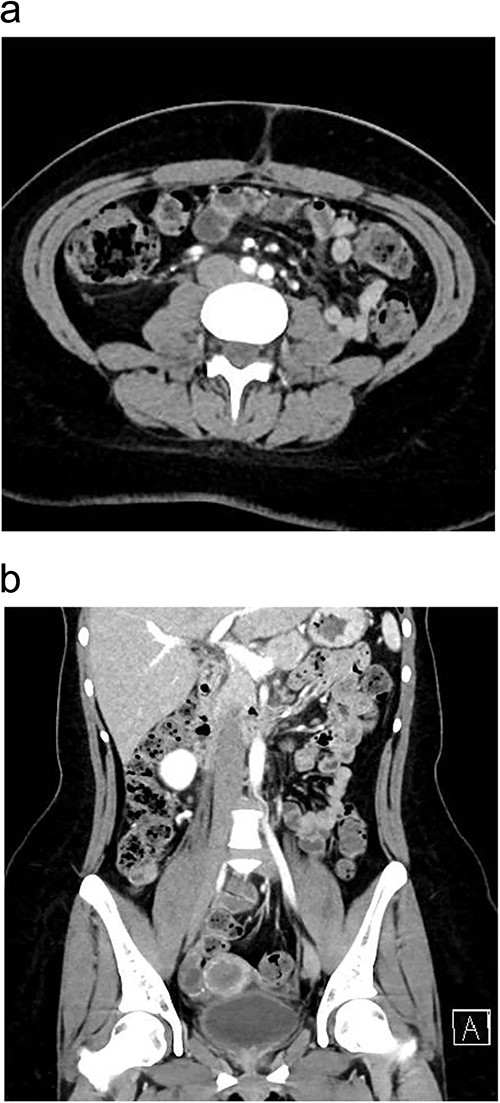

Upon presentation, the patient was vitally stable except for a low-grade fever (37.8°C). Her abdominal examination revealed tenderness in the paraumbilical and right lower quadrant regions with positive rebound and Rovsing signs. Abdominal X-ray was unremarkable. Laboratory investigations revealed leukocytosis (Table 1). Enhanced CT scan of the abdomen and pelvis revealed signs of appendicitis with a moderate amount of free fluid (Fig. 1a and b).

Preoperative enhanced CT abdomen and pelvis with axial (a) and coronal (b) views showing dilated appendix with hyperdense appendicolith within its lumen (arrow) associated with surrounding fat stranding and moderate amount of free fluid of −7 to 0.4 Hounsfield Units density.